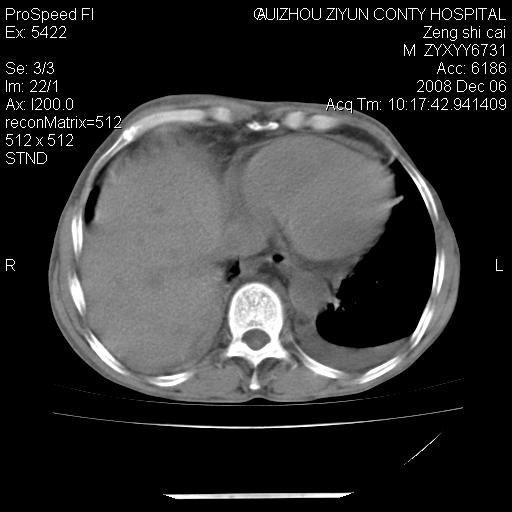

标题: CT16961:M、71岁,咳嗽半年,无血痰;胸片示右肺占位。 [打印本页]

标题: CT16961:M、71岁,咳嗽半年,无血痰;胸片示右肺占位。

升结肠癌伴腹膜后淋巴结转移

右肺癌并纵隔淋巴转移,腹膜后转移可能性大,两侧胸腔积液

右肺纵隔型肺癌伴纵隔淋巴结及胸膜转移